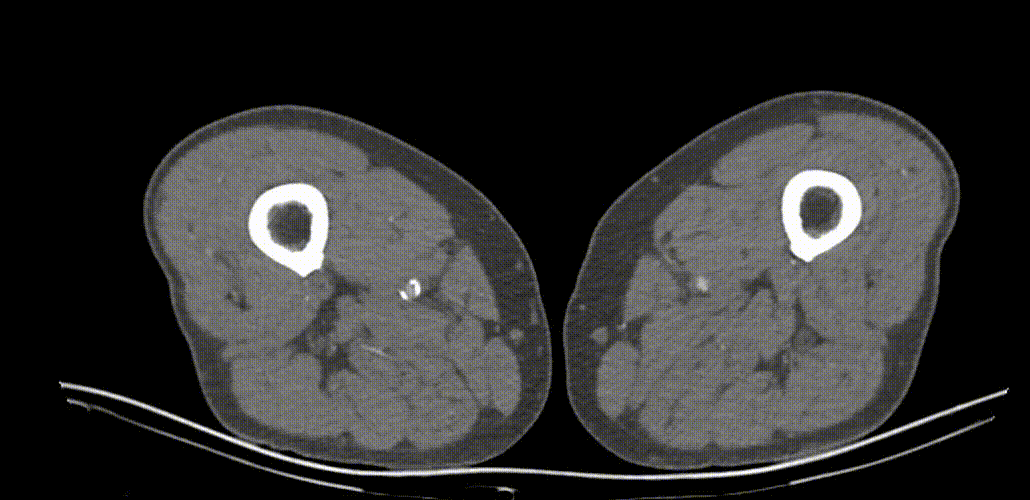

经导丝送入IVUS导管,股浅动脉近段重度狭窄、钙化明显,狭窄率大于90%

股浅动脉中远段及腘动脉重度狭窄、环周钙化明显

因患者股浅动脉及腘动脉狭窄闭塞段均严重钙化,选择使用振波球囊(6mm*80mm、5mm*80mm)